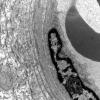

PERIPHERAL NEUROPATHY

11 VASCULITIS - VASCULOPATHY

2 Vasculopathy (7)